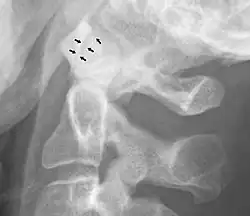

La Osteoartritis puede producirse en la articulación atlanto-axial.[4] Se trata de la clásica fisiopatología, como la pérdida de cartílago articular, los osteofitos visibles con la radiografía y el engrosamiento del hueso con un espacio articular estrecho.[4] El tratamiento conservador suele ser eficaz, e incluye analgésicos.[4] La cirugía puede utilizarse en casos graves, y puede tener buenos resultados.[4]

Ampliación anormal

Un ensanchamiento de la articulación atlanto-axial, medido entre la superficie posterior del arco anterior del atlas y la parte anterior de la apófisis odontoides, indica una lesión del ligamento atlantal transverso.[5] Normalmente, esta distancia atlanto-axial es inferior a 2 mm, a veces se acepta un máximo de 3 mm en los hombres y 2,5 mm en las mujeres.[5]